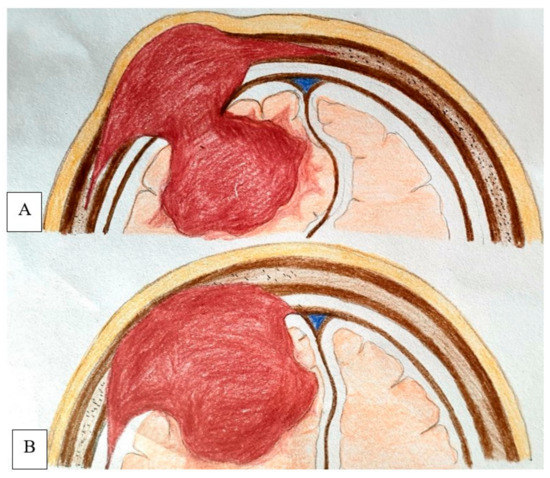

2.4.4. Surgical Procedure

4.6. Extent of Dura and Soft Tissue Involvement

4.7. Recommended Management Strategy